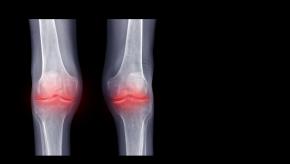

Rheumatologists typically manage systemic autoimmune rheumatic diseases (SARD) and associated interstitial lung disease (ILD) with immunosuppressants. However, evidence increasingly supports also the use of antifibrotic agents in this setting.

The COLCHICORT trial in acute calcium pyrophosphate (CPP) crystal arthritis patients showed that colchicine was inferior to prednisone treatment and that responses were also influenced by other factors.